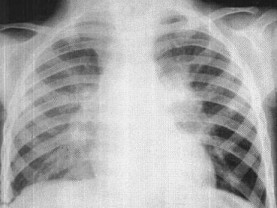

女,3岁,低热、咳嗽2月余,结合胸片,最可能的诊断为()